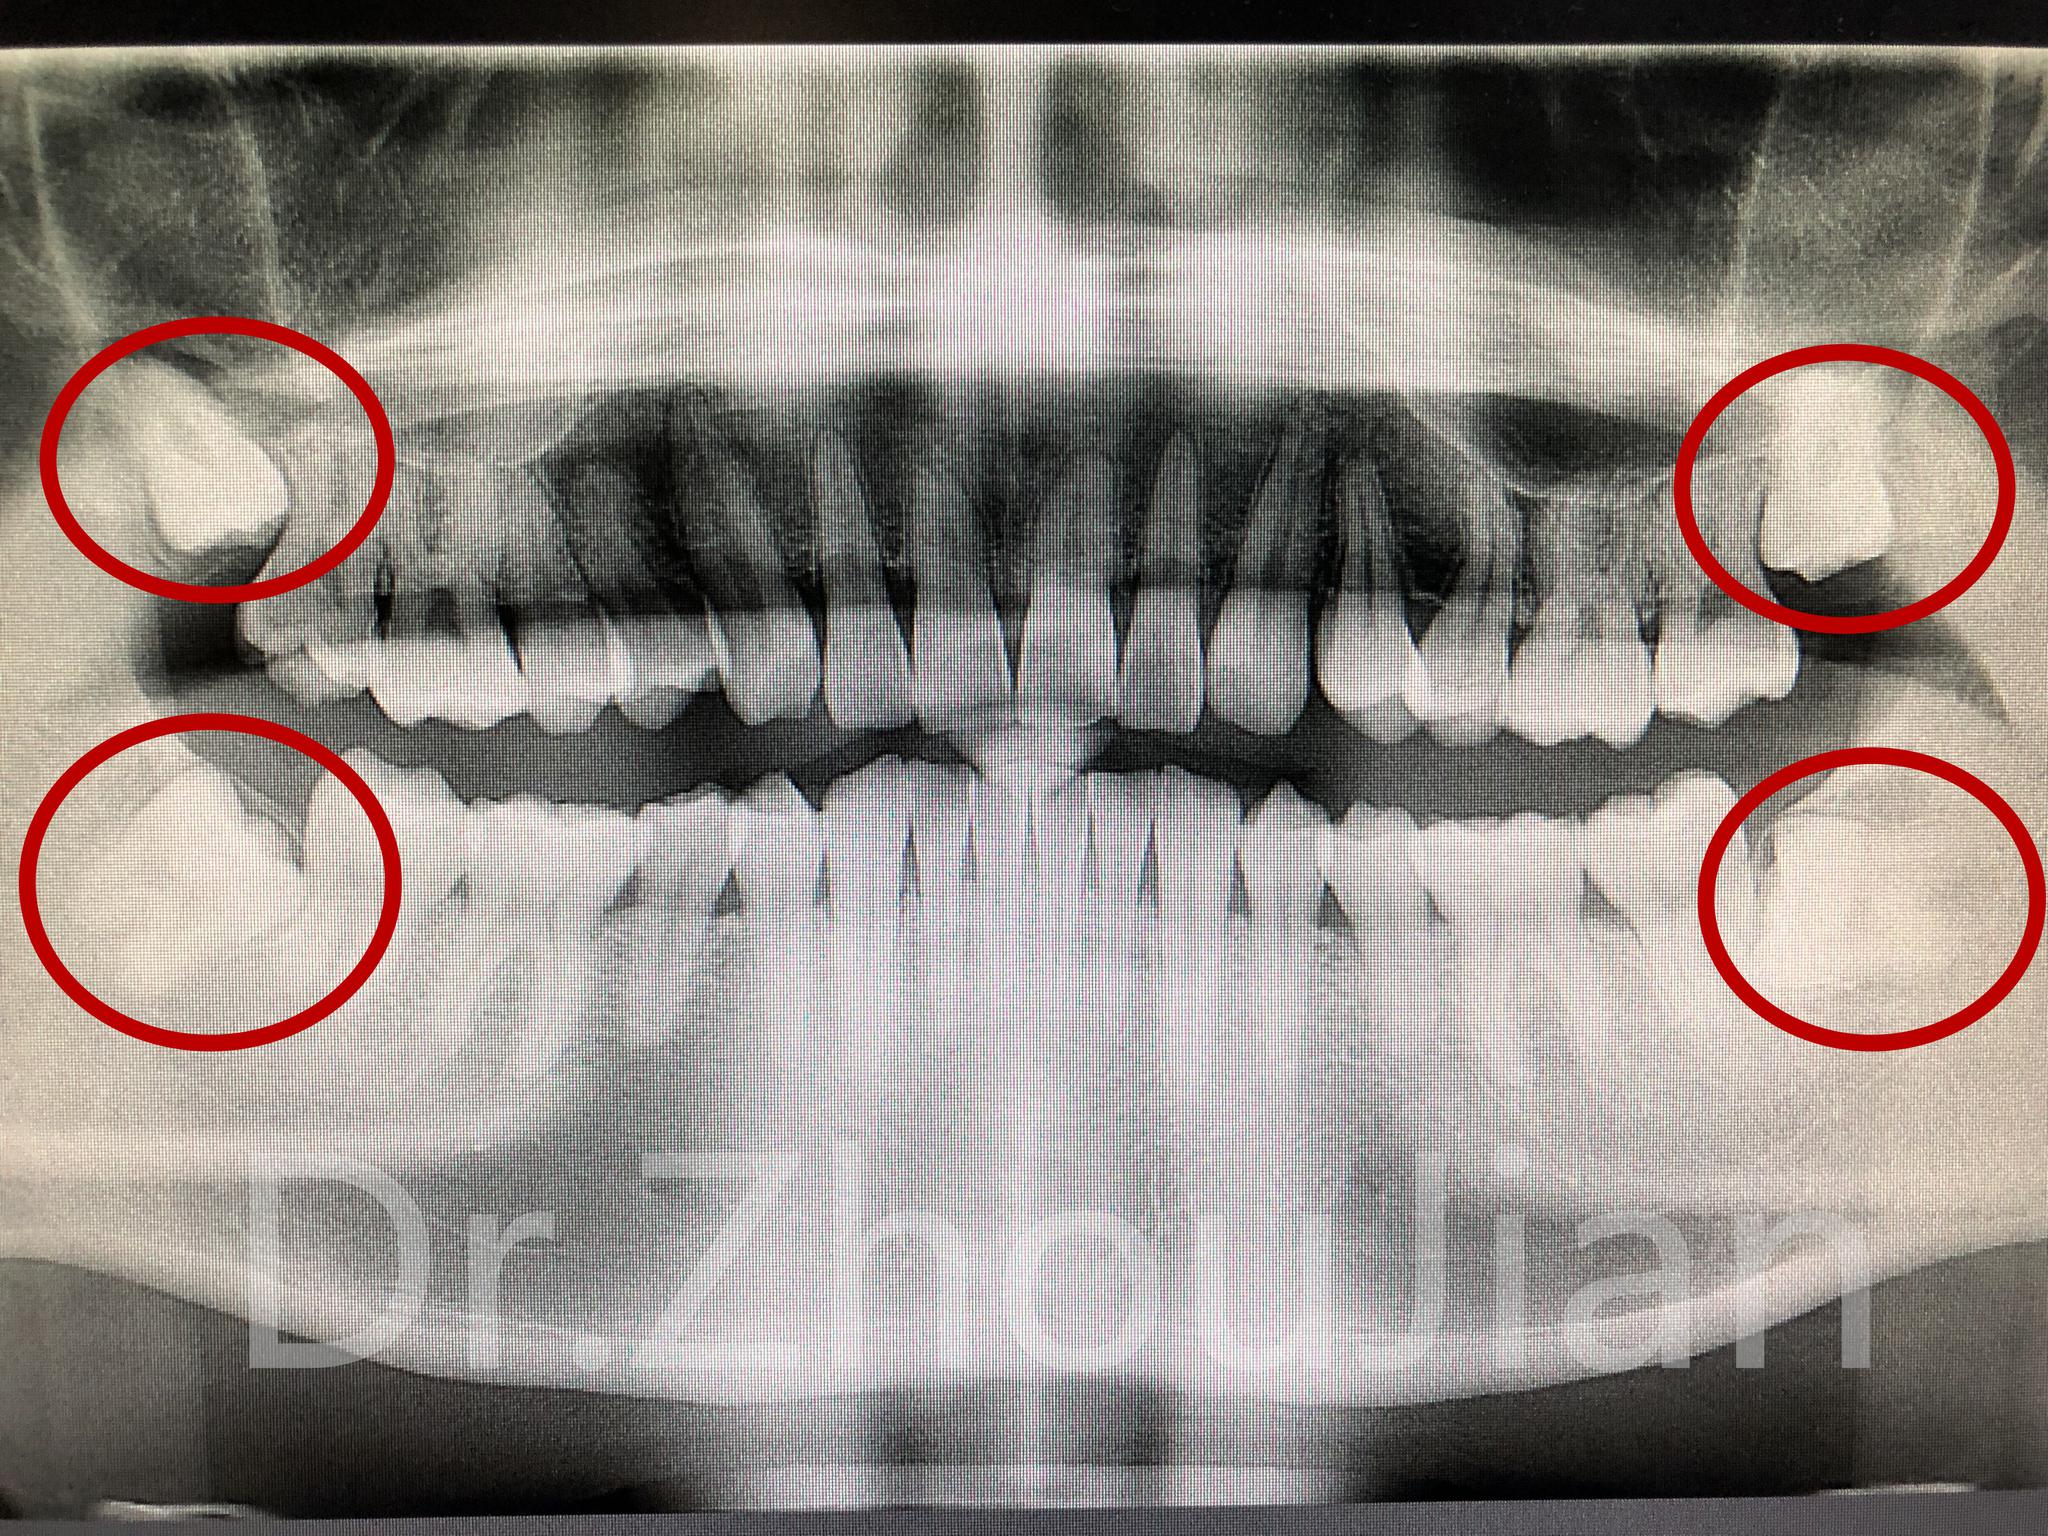

简介:口腔CT可以从三维角度对组织情况进行反映,可以发现口腔X光片的投照角度不能发现的、或者更细微的病变;它

你好,根据你描述的情况,考虑是牙齿的阻生问题。建议到医院找口腔科大夫看看,可能需要拍口腔ct。看看牙齿的形态及牙根的情况。口腔ct的价格一般在300元到500元之间。

牙齿如果出现蛀牙要及时去检查补牙齿,避免蛀牙越来大,牙齿若出现蛀牙坏了。不但影响美观,还会影响牙齿健康,很多人不知道牙CT和牙片的区别有

你好,牙片就是X线片,和CT的区别,CT的检查要清晰的多,如果平常生活条件好的话,都是建议做CT检查,因为CT检查可以看到很多细小的地方,如果家庭条件不太好的话,牙片检查就